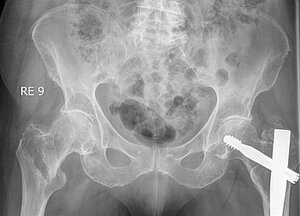

Beckenübersicht mit frischem Schenkelhalsbruch rechts und operativ versorgtem Schenkelhalsbruch links